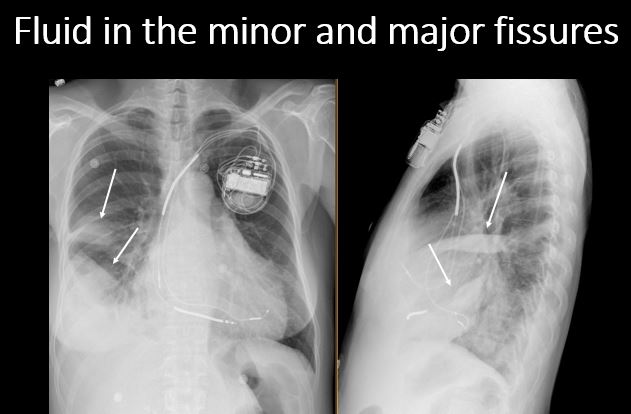

Section 1 Submit Findings Case322 Findings Technique The exam is expiratory, rotated, over or under penetrated, or limited by overlying structures or soft tissues, body habitus, patient positioning, or motion. Yes No Support Devices There is a vascular line or lines present in an abnormal location or otherwise abnormal. Yes No There are other devices such as a chest tube or pleural drain, feeding, NG, or gastrostomy tube, LVAD or pacemaker, vascular stents, cardiac valves, anesthesia catheter, VP shunt, neurostimulator, or other drains or tubes present that are in an abnormal position or are otherwise abnormal. Yes No Cardiomediastinum The superior mediastinum is abnormally widened considering the technique. Yes No There is abnormal shift of the mediastinum. Yes No There is a mass or other abnormal density in or overlying the mediastinum. Yes No There is an abnormality in the retrosternal, retrotracheal, or retrocardiac space on the lateral view. Yes No There is abnormal tracheal deviation or narrowing on the frontal and/or lateral view. Yes No There is pneumomediastinum and/or pneumopericardium. Yes No There is enlargement of the cardiac silhouette. Yes No The heart borders are abnormal. Yes No The right paratracheal stripe is thickened or enlarged. Yes No The azygoesophageal recess is displaced or otherwise obscured. Yes No Vasculature and Hila The aorta is dilated, tortuous, ectatic, calcified, or there is a focal contour abnormality. Yes No The central pulmonary arteries or hila are enlarged. Yes No The aorto-pulmonary window is convex or obscured by a mass, adenopathy, or vasculature. Yes No There is cephalization or haziness of the pulmonary vessels or congestion of the central pulmonary vasculature. Yes No Lungs The lungs are hyperinflated or underinflated generally or segmentally. Yes No There is focal, multifocal, or diffuse airspace disease, mass, opacity, or nodularity. Yes No There is focal or diffuse interstitial disease. Yes No There is focal or lobar atelectasis or total collapse of the lung. Yes No There is cavitary or cystic disease with or without air fluid levels or soft tissue nodularity. Yes No The position of the major and minor fissures is abnormal. Yes No The right or left hemidiaphragm is focally or diffusely obscured on the frontal and/or lateral view. Yes No There is elevation, depression, or contour abnormality of the right or left hemidiaphragm. Yes No Pleura There is focal or diffuse abnormality of the pleura or chest wall. Yes No There is a pleural effusion, blunting of the costophrenic angle, or posterior sulci. Yes No There is focal fluid in the fissures. Yes No There is asymmetric pleural thickening or capping of the apices. Yes No There is a pneumothorax, hydro/pneumothorax, or hemo/pneumothorax. Yes No Bones, Soft Tissues, Upper Abdomen The ribs, clavicles, shoulder, spine, or other visualized bones are abnormal. Yes No There is free air beneath the diaphragm. Yes No The bowel or organs of the upper abdomen are abnormal. Yes No There is subcutaneous emphysema, focal or diffuse soft tissue abnormality, radiopaque foreign body, or post-surgical change or hardware. Yes No